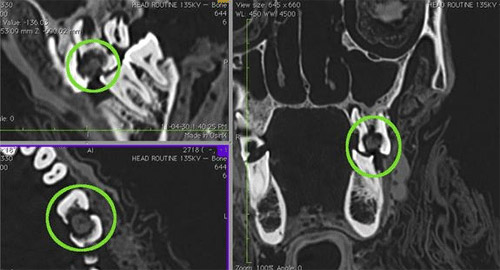

Những hình ảnh chụp CT cho thấy hàm răng của người thanh niên này vô cùng khủng khiếp, khoang áp xe răng bị nhiễm trùng túi, dẫn đến viêm xoang.

Phân tích hình ảnh chụp CT với độ phân giải cực cao cho thấy các nha sĩ cổ đại đã chữa răng bằng cách bổ sung nước trái cây hoặc dầu cây tuyết tùng, vốn vẫn còn vón lại trong lỗ sâu răng. Phương pháp trên nhằm tạo ra rào cản để ngăn chặn các hạt thức ăn lọt vào lỗ sâu răng, sẽ giúp giảm đau cho bệnh nhân. Nhưng đáng buồn thay, phương pháp ấy cũng chỉ giúp người đàn ông này chống chọi một thời gian ngắn, có lẽ chỉ trong một tuần, vì nó khiến vi khuẩn có thể lây nhiễm nhanh chóng hơn.

Phân tích hình ảnh chụp CT của xác ướp